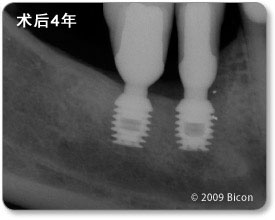

避开下齿槽神经管

用三个5.0 x 8.0mm和一个6.0 x 5.7mm短种植体修复下颌后牙的四年追踪。注意下齿槽神经管的水平。   短种植体支撑一体化基台冠修复两颗右下颌磨牙。注意下齿槽神经管的水平。